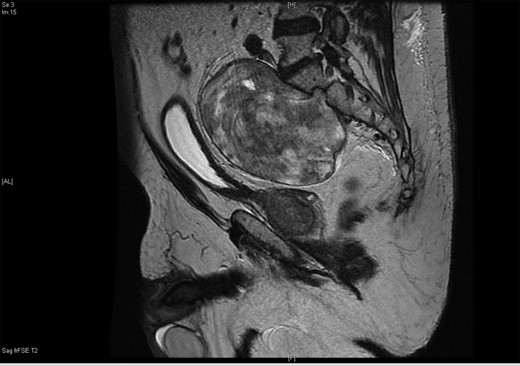

A 71-year-old asymptomatic gentleman with known history of colonic polyps underwent a follow-up surveillance colonoscopy through the BCSP. He had a background of type 2 diabetes mellitus, ischaemic heart disease and diverticular disease. Colonoscopy revealed a 1-cm firm polypoid mass at the ano-rectal junction (Fig. 1). Subsequent endoscopic mucosal resection was performed and the tissue was sent for histological analysis. This confirmed a tubulo-villous adenocarcinoma. As per national guidelines the patient underwent a staging computed tomography (CT) scan. This revealed a 10 × 15 cm homogenous mass arising from within the pelvis (Fig. 2). The mass appeared to be continuous with a neural foramen arising from the sacrum. Further imaging confirmed the mass extending into sacral segment S1 inferiorly, lumbar segments L4 superiorly and the bladder anteriorly. A regional multidisciplinary team discussion concluded that abdominoperineal resection (APR) was the most appropriate surgical approach for removal of both pathologies in their entirety.

The 10 × 15 cm pre-sacral pelvic mass on sagittal contrast CT.